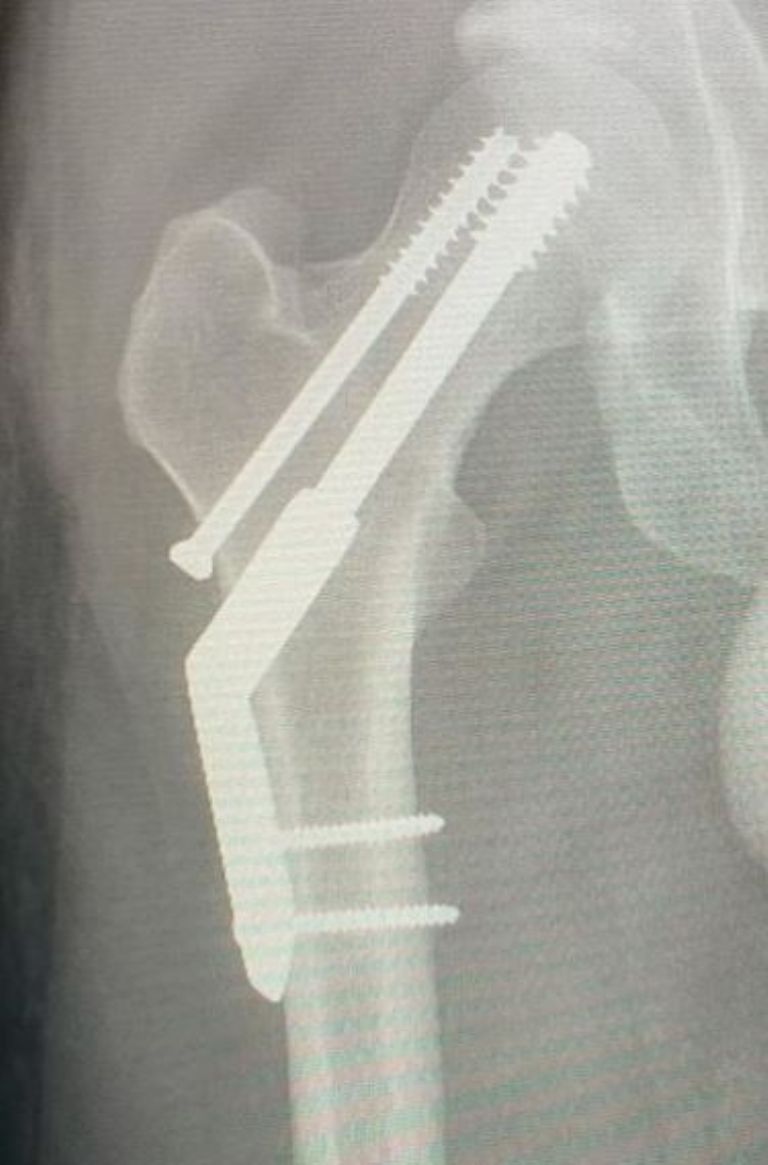

Parker compartió una serie de fotografías acostado en una cama de hospital, así como algunas máquinas e incluso mostró sus radiografías en donde se alcanzan a ver los clavos que lo ayudan a unir sus huesos. Kevin relató en Instagram que todo se debió a que intentó correr un maratón, lo que trajo como consecuencia este inesperado accidente: "Me fracturé la cadera. Intenté correr una media maratón en lo que resultó ser una fractura de estrés existente".

Créditos: Instagram @tameimpala